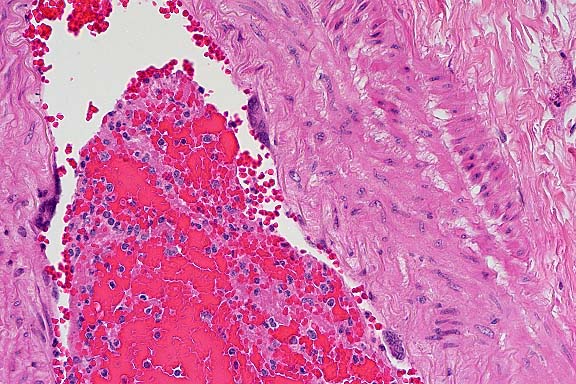

- Case 5- 2. Lung. The pleura and interlobular

septa are markedly expanded by clear space (edema) and scattered

lymphocytes an plasma cells. A pleural arteriole has fibrinoid

degeneration and necrosis of its walls with infiltrating and

adjacent lymphocytes and plasma cells.

- 1. Lung: Vasculopathy, characterized by endothelial syncytia,

mural necrosis, fibrinoid change, subacute perivasculitis, and

moderate interstitial edema, breed unspecified, equine.

- 2. Kidney, interstitial and glomerular blood vessels: Vasculopathy,

characterized by endothelial syncytia, mural necrosis, and fibrinoid

change.